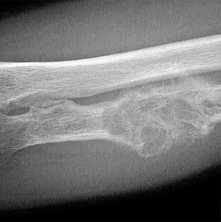

о Нейропатический акроостеолизис, может быть сильно выраженным и вовлекать большой объем костной ткани, помимо дистальных фаланг (20-70% случаев госпитализации)

о Остатки периферической кости могут иметь очень острый или тупой угол

о Нейрогенная артропатия лучезапястного или голеностопного сустава

о Периостит, остеомиелит (редко; 3-5% случаев госпитализации)